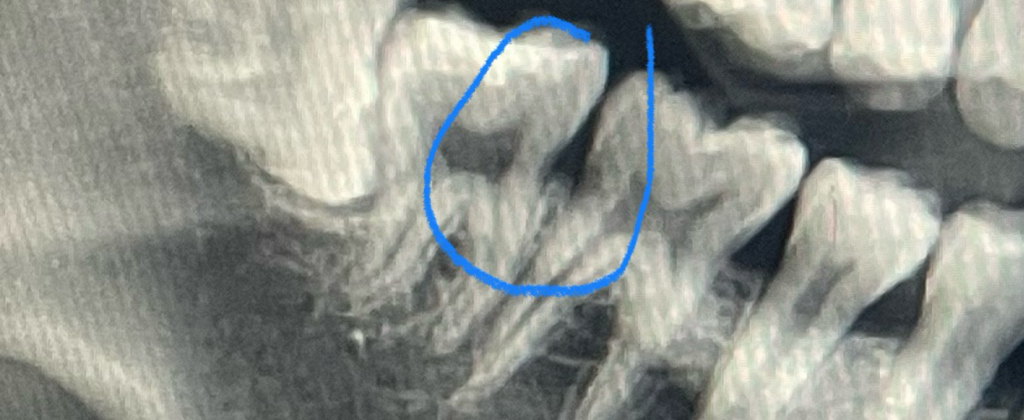

충치인지 아닌지 궁금합니다..

의사 선생님께서는 전체적으로 문제없다고 하셨는데 이 부분이 검은게 좀 신경쓰여서요 차가운거 먹을때 살짝 시리기도 합니다 충치처럼 보이나요?

앞니쪽에 충치가 잇는것같습니다. 저부위가 시리다면 신경과 가까워서 신경치료를 해야될 가능성도 있어 보입니다.

치아 사이는 검게 나오기도 합니다

파노라마가 아닌 정밀 사진 찍어보시면 더 정확한 정보를 알 수 있습니다

해당 부위 검정색으로 보이는 부분은 치경부 소환이라는 방사선 사진 상 현상으로, 충치가 아닐 가능성이 높습니다만, 임상검사 및 치근단방사선사진촬영을 하여야 정확히 알수 있습니다.